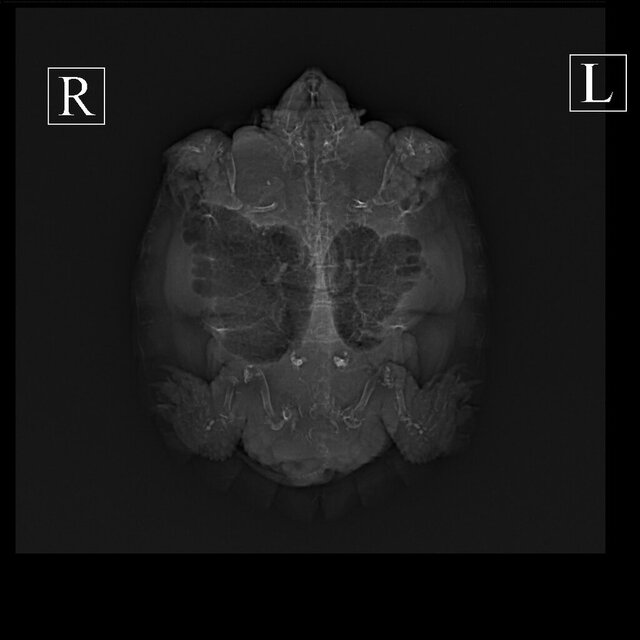

Вы рентген сможете ей сделать? нужен в 3х проекциях. Рентген можно в любой ветклинике сделать где согласятся. Для этого герпетолог не нужен

Сделали рентген. Готовы к онлайн консультации

Есть другой формат рентгена, но сюда не получится выложить

IMG-20230518-WA0002.jpg

IMG-20230518-WA0001.jpg

IMG-20230518-WA0000.jpg